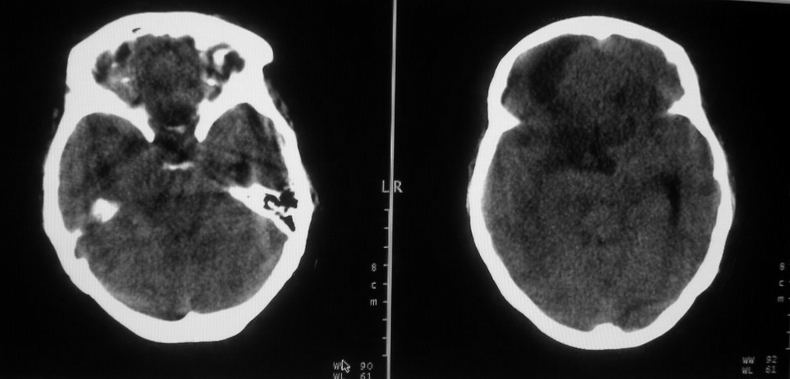

女,44岁,头痛数月。

右侧额叶占位性病变,考虑脑肿瘤;建议行进一步检查。

右侧额叶占位性病变,考虑脑膜瘤可能性大;建议行进一步检查。